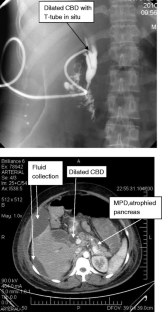

Fig. 1